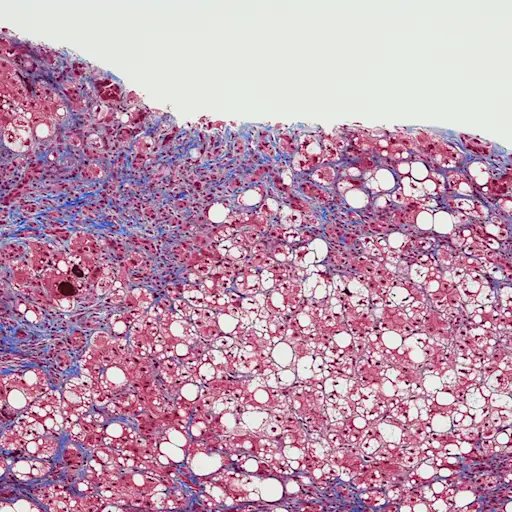

丙型肝炎肝脏损害如何

丙肝病毒感染和肝细胞死亡,细胞在肝脏,医学博士杰弗里·d·块解释道肝脏移植手术的医务主任在图森亚利桑那大学医学院。这引发炎症反应。的肝脏在超速工作创造更多的健康细胞并释放免疫细胞(细胞因子)来对抗病毒,疤痕组织积累。随着时间的推移,持续的免疫反应导致如此多的疤痕组织建立恰当地称为肝硬化,肝脏不能函数。当这种情况发生时,以下9个并发症可以弹出。